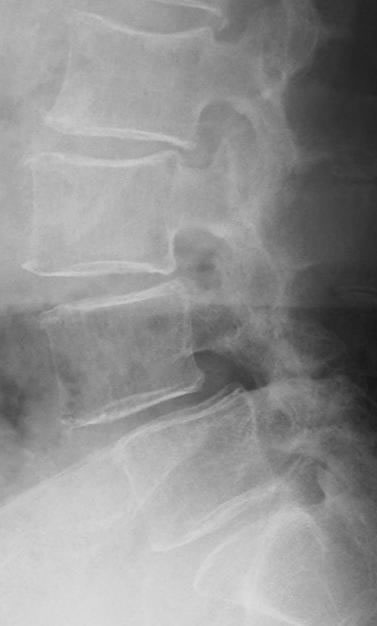

不安定性を擁している 腰椎すべり症のレントゲン